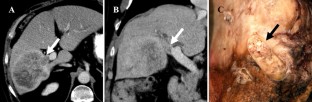

Fig. 1